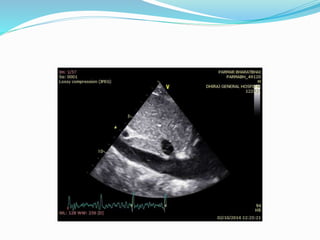

ECHOCARDIOGRAPHY

 2D echo:

 Pericardial thickening (TEE more sensitive)

 Normal RV and LV chamber size

 LA and RA enlargement

 Abnormal septal and posterior wall motion

 Paradoxical septal motion

 Premature opening of the pulmonic valve

 Dilated IVC without respiratory variation